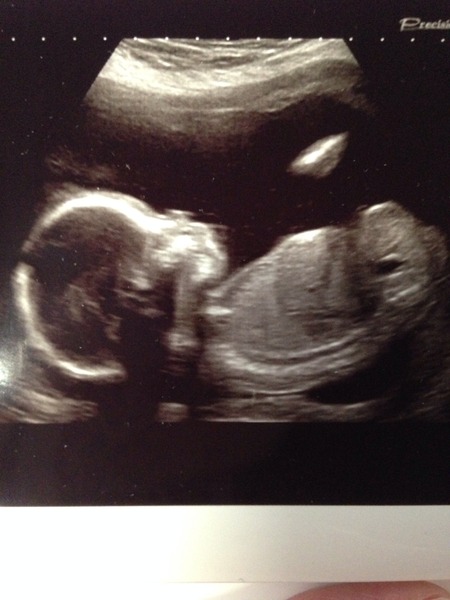

Nessalina · 17/06/2014 19:50

Alreet ladies Grin

Scan was good! Hurrah! We went in bang on time which helped with the bladder, but she was only scanning for 5mins before she said 'actually, your bladder is a little too full, do you want to go for a wee'? I've never jumped up so quick in my life! Lol. We had to have a break halfway through because baby was squirming all over and wasn't staying in the right place long enough for her to check his spine, so she sent me off for a walk and a glass of water. Second time he was better behaved, and we got some decent piccies!

Lovely scan picture, Ness. Did you find out the sex?

That pic is great nessa, very clear. It's a little person! I bet you can't stop grinning!